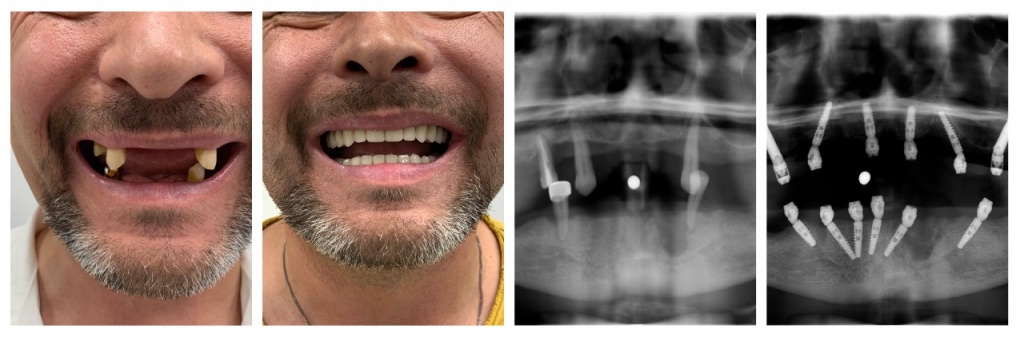

Появление инновационной процедуры протезирования все-на-4 или все-на-6 открыло перед стоматологами и их пациентами новые возможности. Теперь имплантацию зубов можно провести за один день, сократив реабилитационный процесс до минимума.

В данном случае дантист устанавливает в ротовую полость пациента несъемную конструкцию, которая крепится на 4 или 6 имплантов (все-на-4 или все-на-6 соответственно). Протез может быть установлен сразу после завершения процедуры удаления. Снять конструкцию без помощи стоматолога будет невозможно.